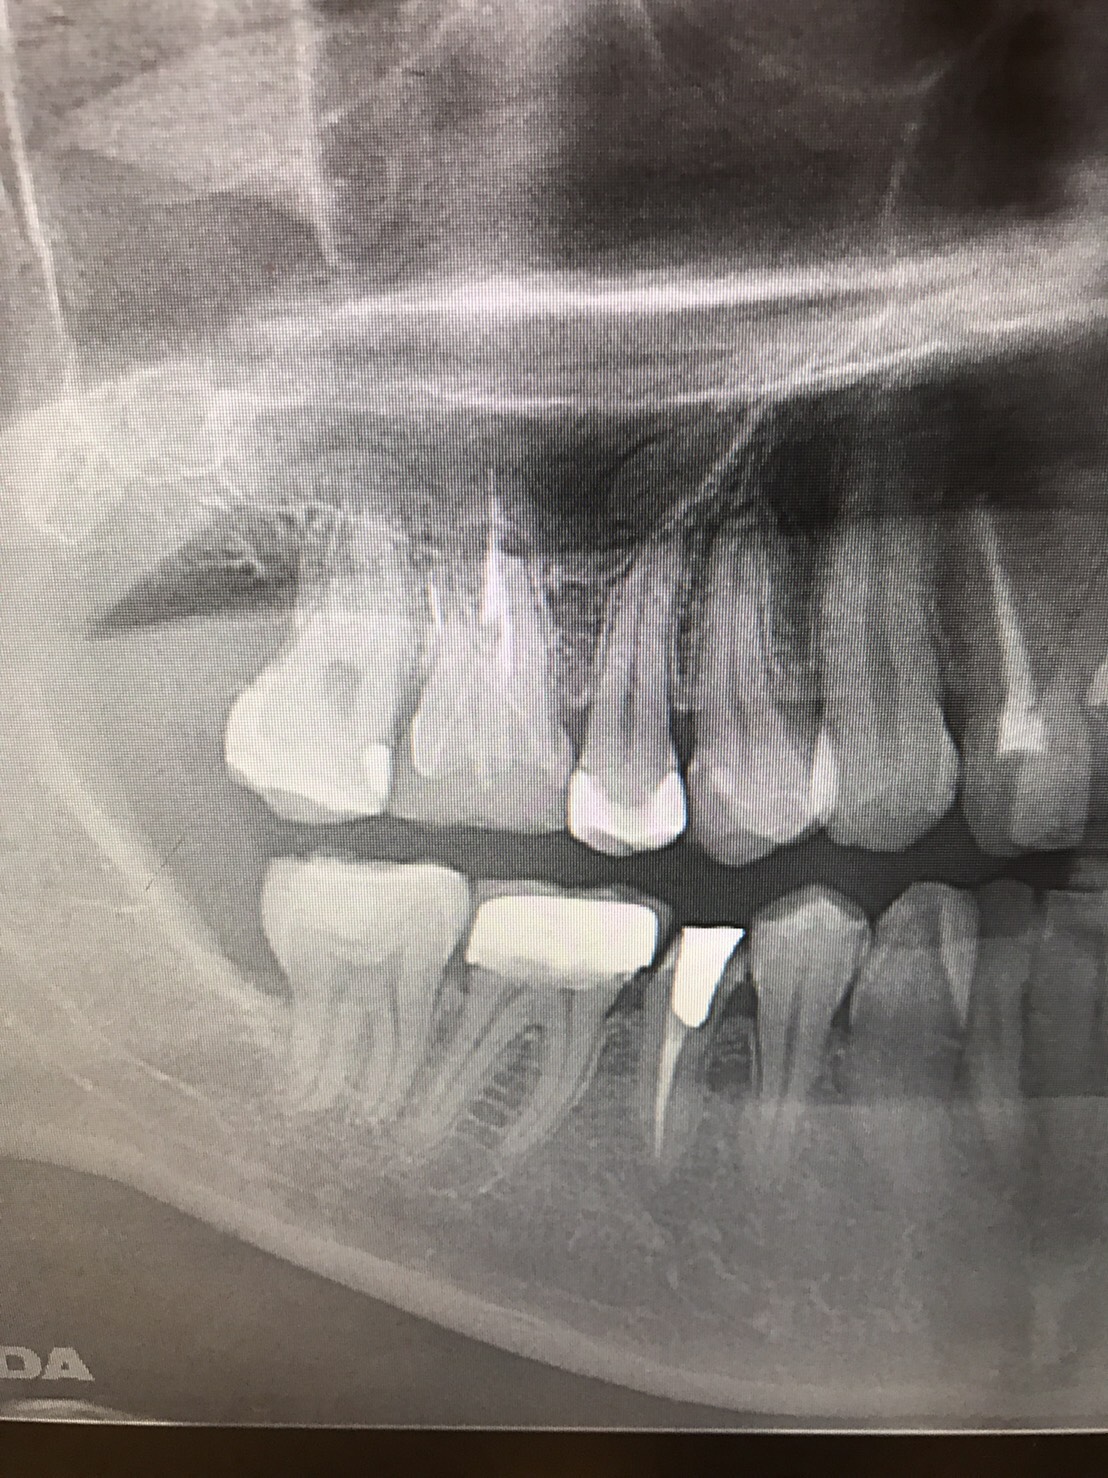

「ずっと放置してしまっていた。今回はちゃんとしっかり治したい」ということで、強い意志をもって来院してくださった患者様の症例です。

インプラント治療、セラミック治療、歯周病治療により、審美性と機能、咬みあわせの再建を行いました。

患者様は咬みあわせの確立により、食事もしやすく、普段の顎関節の状況も良くなり、機能の回復にも満足してくださり、また審美性も喜んでくださいました。

放置期間が長くだいぶ骨が溶けてしまっていたので、前歯部のインプラントは骨の再生療法などが必要だったりしましたが、患者様が治療への前向きな姿勢をだしてくださっていましたので期間も最短で終わりました。

一度放置してしまうと、億劫になってしまってなかなか行動に移すのは難しいと思いますが、少しでも早く治してあげた方が毎日の食事も楽になりますし、お顔の見栄えもお顔の骨格の歪みも改善します。